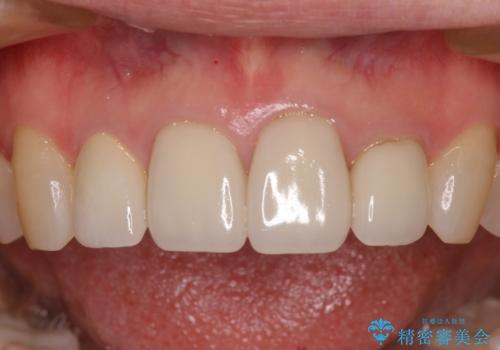

欠けてしまったセラミッククラウン 周囲のクラウンと同様の色彩で再製作

- 上顎4前歯に装着されているセラミッククラウンのうち、ひとつが欠けてしまったとのことで来院された患者様です。

土台となっている歯には問題がないため、周囲のセラミッククラウンと色調が合うように、オーダーメイドタイプのセラミッククラウンにて補綴治療を行うこととしました.

欠けてしまったセラミッククラウンはガラス系セラミッククラウンであったため、今回製作する歯は、強度の強いジルコニアセラミッククラウンとしました。

クラウンの種類は異なりますが、色調の適合したクラウンを装着することができました。